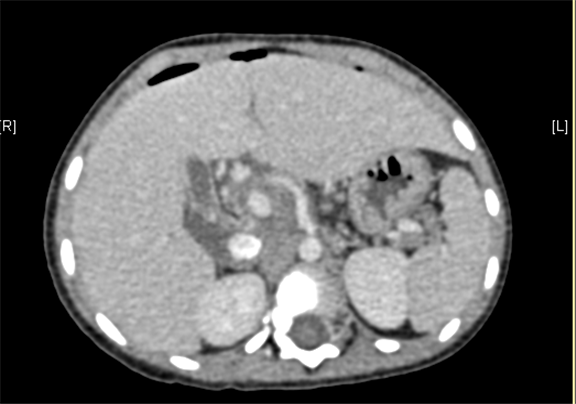

术前CT检查:

动脉期

上腹部增强CT提示肝门处占位性病变,考虑腹膜后肿瘤可能性大,畸胎瘤? AFP 11.38ng/ml